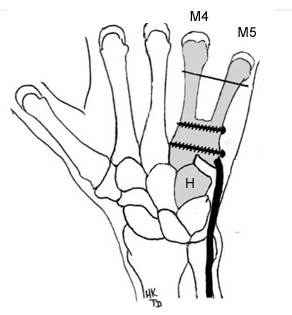

La technique que je recommande est l’arthroplastie-stabilisée